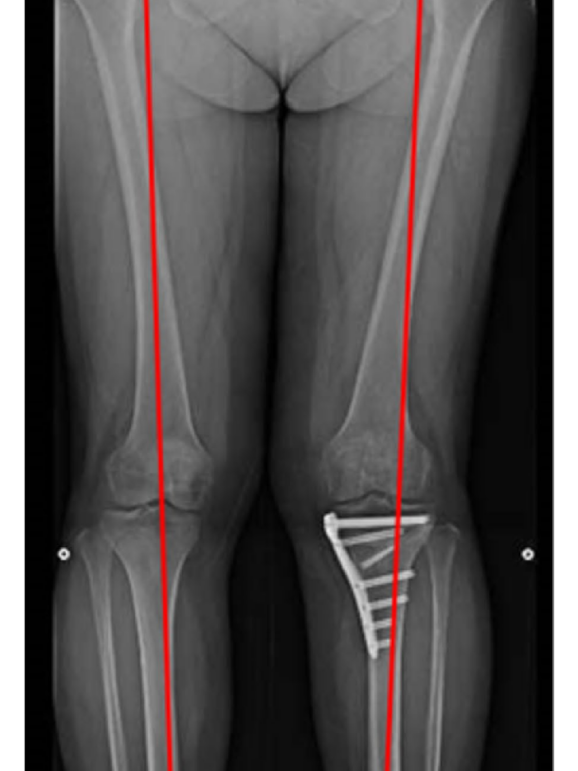

Knee Preservation

Total Knee Replacement (TKR) Package – Implant Based Cost Guide